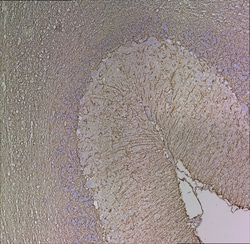

GFAP Monoclonal Antibody for Western Blot, ICC/IF, IHC (P)

GFAP (Glial fibrillary acidic protein) is a member of the class III intermediate filament protein family. GFAP is heavily and specifically expressed in astrocytes and certain astroglia of the central nervous system, in satellite cells of peripheral ganglia, and in non-myelinating Schwann cells of peripheral nerves. In addition, neural stem cells strongly express GFAP. Antibodies to GFAP are very useful as markers of astrocytic cells. In addition, many types of brain tumor, presumably derived from astrocytic cells, heavily express GFAP. GFAP is also found in the lens epithelium, Kupffer cells of the liver, in some cells in salivary tumors and has been reported in erythrocytes. GFAP is used as a marker to distinguish astrocytes from other glial cells during development. Mutations in this gene cause Alexander disease, a rare disorder of astrocytes in the central nervous system. Alternative splicing of the GFAP gene results in multiple transcript variants encoding distinct isoforms.Specifications